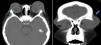

Tomografía de cráneo contrastada realizada tras 3 semanas de evolución, muestra imagen axial (A) y coronal (B) donde se identifica colección palpebral bilateral (flecha azul) de 42,75×14,88 mm en el párpado derecho y de 47,16×21,70 mm en el párpado izquierdo, sin afectación de la órbita. Se observa compromiso de los senos etmoidales y en el área donde inician su formación los senos frontales, además de reacción perióstica frontal.